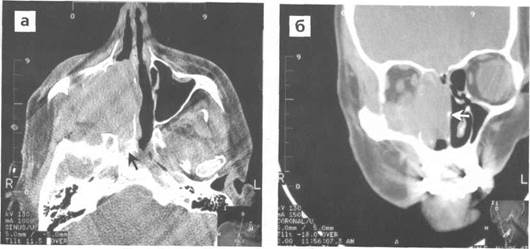

Рис. 2Предоперационная КТ PNS. В правой верхнечелюстной пазухе наблюдается куполообразная рентгеноконтрастность

Описанные жалобы не всегда являются признаком именно кисты, поэтому в большинстве случаев необходимы консультация оториноларинголога и выполнение томографии околоносовых пазух. Наиболее значимыми методами диагностики являются компьютерная или магнитно-резонансная томография придаточных пазух носа, позволяющие с точностью до миллиметра установить размер кисты, ее расположение в пазухе.